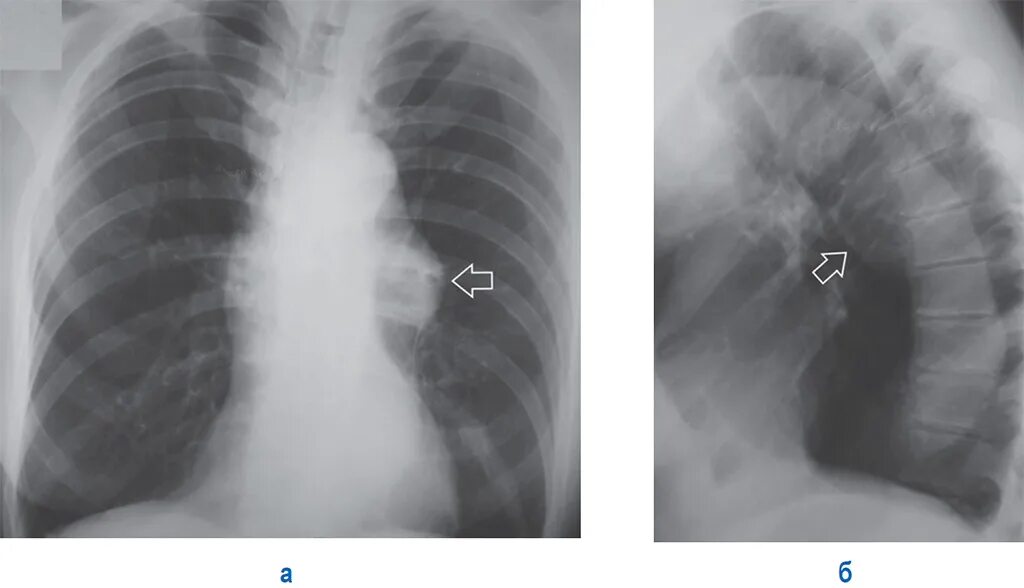

Что значит аорта уплотнена на флюорографии